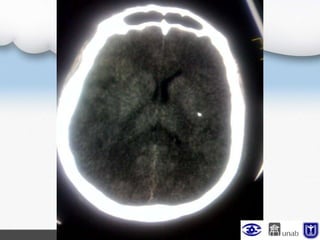

TAC de control

Se observa compromiso de 2/3 de la ACM derecha con

edema perilesional, compresión de

ventrículos laterales ipsilaterales se considera

debido a la edad del paciente, riesgo de edema

cerebral maligno, con criterios de

craniectomía temprana: edad, hemisferio no

dominante y edema, se sugiere valoración por neurocirugía

Escanografía cerebral simple con ligero edema

cerebral de predominio derecho con mínimo colapso

del ventrículo lateral ipsilateral.

Actualmente NO cumple criterios para procedimiento

quirúrgico